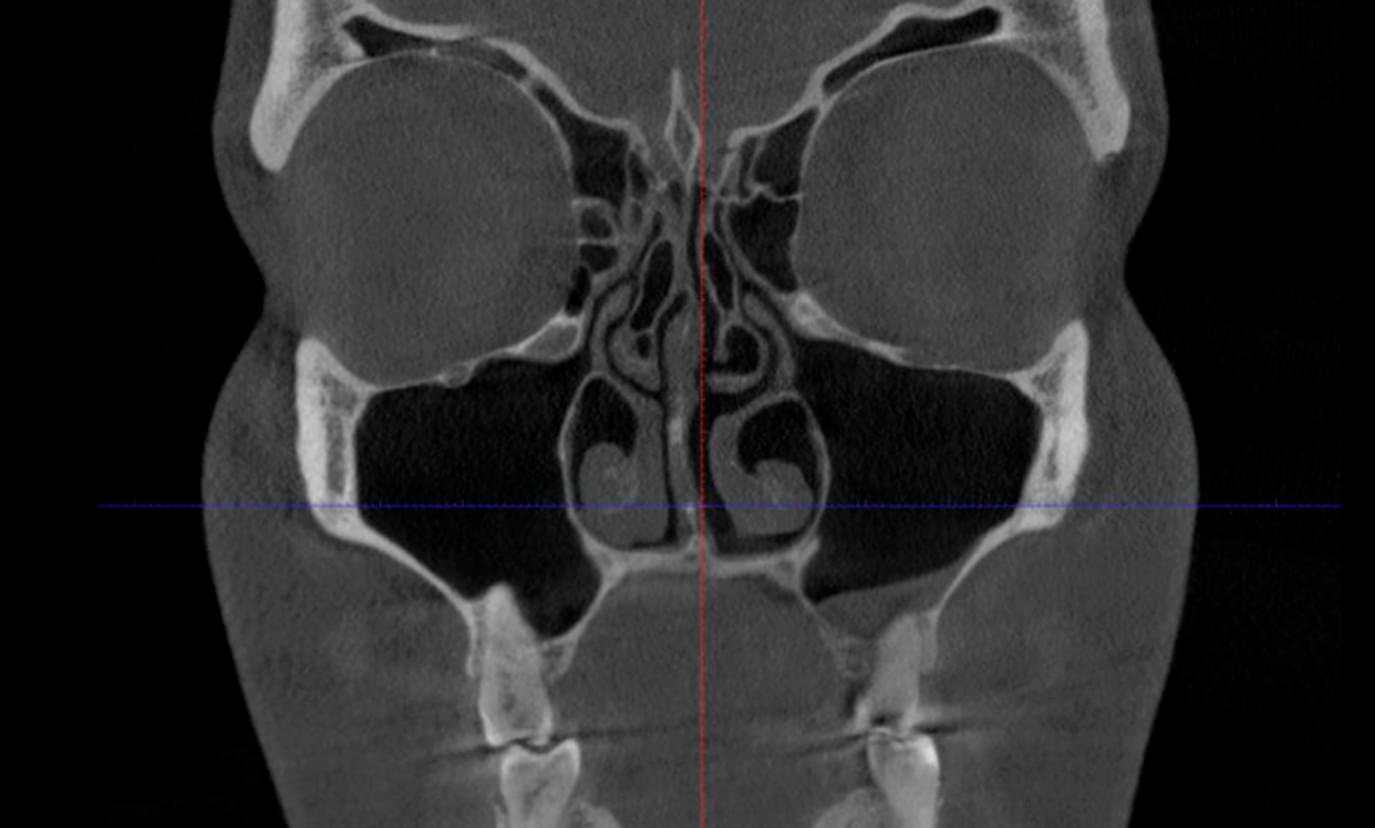

Знімок КТ — це величезний масив даних. Іноді вашому лікуючому лікарю (ЛОРу, стоматологу або хірургу) потрібна допомога вузькопрофільного фахівця — лікаря-рентгенолога, щоб не пропустити жодної деталі. Рентгенологічний опис — це медичний документ, в якому сертифікований лікар-рентгенолог детально описує стан усіх анатомічних структур, виявлених на знімку, та фіксує будь-які відхилення від норми.

🔹 Детальна анатомія: Лікар описує будову кожної пазухи окремо (гайморові, лобні, клиновидні,

решітчасті) — чи вони симетричні, чи правильно розвинені.

🔹 Стан слизової оболонки: Чи є набряки, потовщення, поліпи або кісти, які можуть заважати

диханню, але не боліть.

🔹 Прохідність сполучень (устя): Чи заблоковані шляхи, якими повітря потрапляє в пазухи (це

головна причина хронічних гайморитів).

🔹 Кісткові структури: Стан носової перегородки (девіації, шипи), носових раковин та кісткових

стінок.